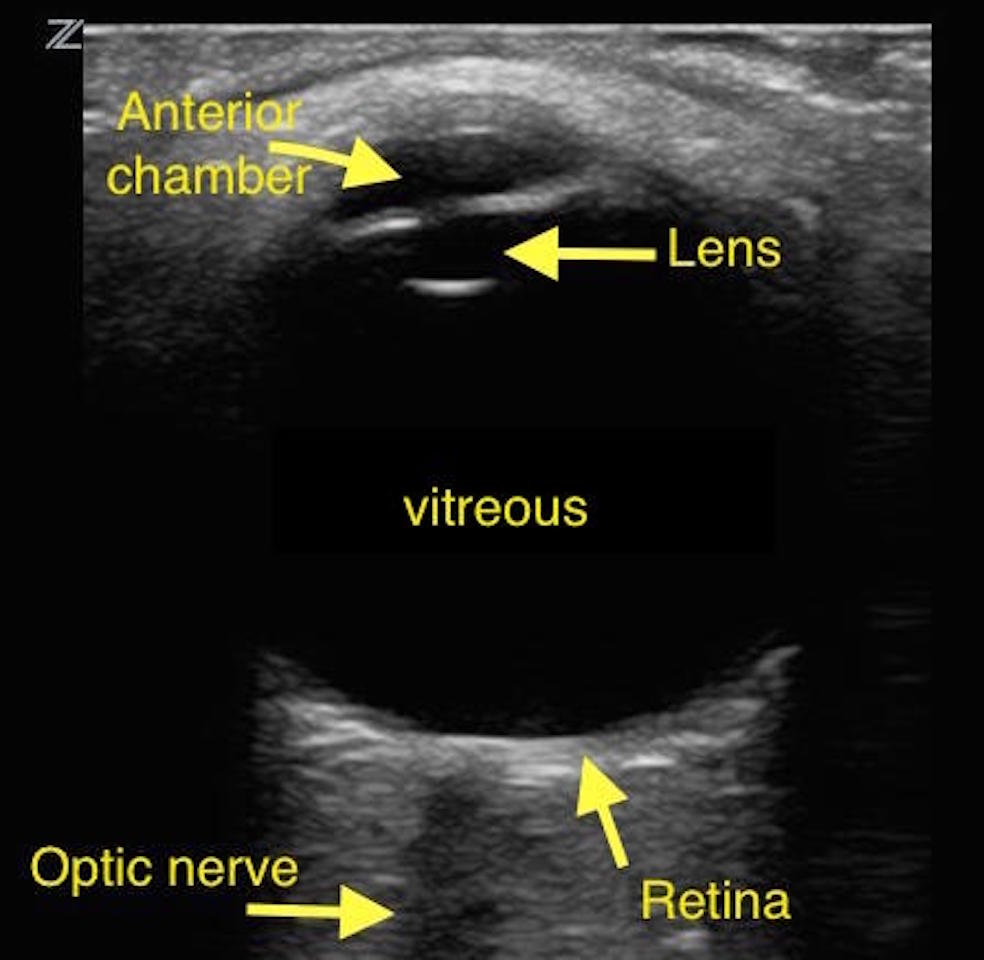

일반적으로 안과에서 사용하는 초음파(ultrasound, sonography)는

10MHz의 주파수, 600um (0.6mm) 의 해상력을 지닙니다.

망막을 포함하는 안구의 뒷부분 및 때로는 안와의 일부를 관찰할수 있습니다.

이를 흔히 B-scan 이라고합니다.